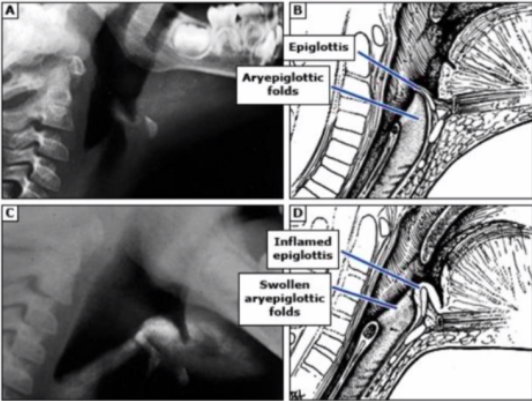

Clínica da epiglotite aguda (3)